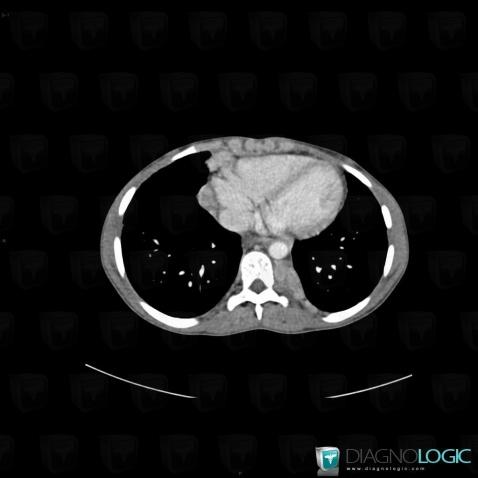

Sarcoïdose, Médiastin, Scanner

Voici les informations spécifiques à l'image clé ci dessus:

- Diagnostic Sarcoïdose, Localisation(s) Médiastin, comportant les gammes Masse de l'angle cardiophrénique